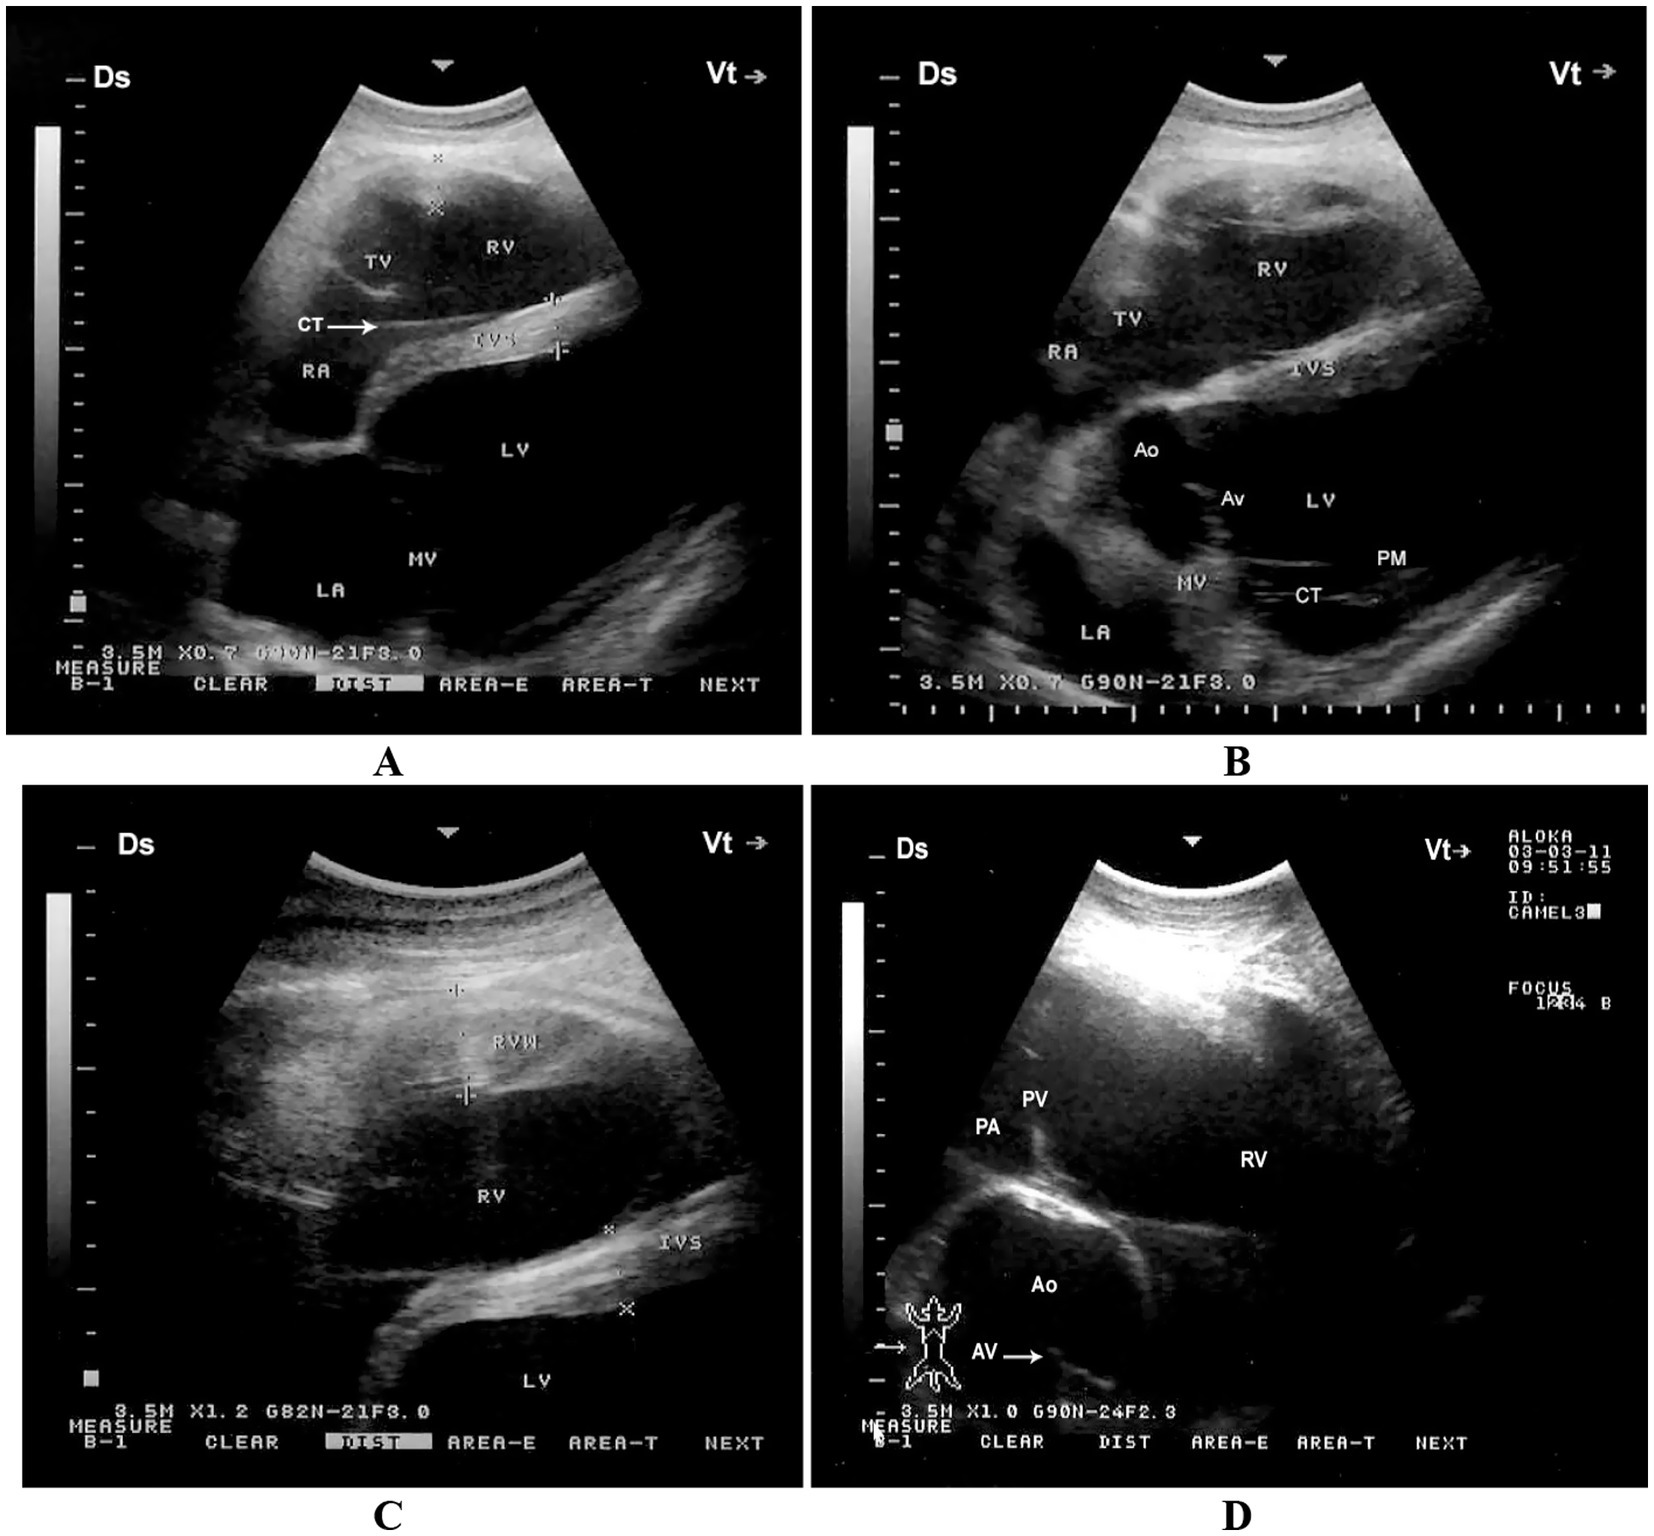

When the probe is positioned longitudinally in the 5th intercostal space (ICS) with a slight clockwise rotation, or placed perpendicularly in the 4th ICS, a caudal long-axis four-chamber view can be obtained. This view includes the right and left ventricles, right and left atria, the interventricular septum, as well as the tricuspid and mitral valves. In some camels, this same position may yield a hybrid view combining features of the four-chamber and left ventricular outflow tract (LVOT) views. A slight clockwise rotation of the probe in the 4th ICS can provide a short-axis view of the cardiac ventricles. Additionally, placing the transducer in the 3rd ICS enables visualization of the right ventricular outflow tract (RVOT), allowing imaging of the right ventricle, pulmonary valve, pulmonary artery, aorta, and aortic valve (11) (Figure 4).

Figure 4. Right parasternal echocardiographic views in a healthy dromedary camel. (A) Caudal long-axis four-chamber view displaying the left and right ventricles with visible tricuspid chordae tendineae (arrow). This view is valuable for assessing chamber size, tricuspid valve morphology, and right ventricular function. (B) Caudal long-axis view including the left ventricular outflow tract, allowing evaluation of aortic valve function and potential outflow obstructions. (C) Short-axis view at the level of the ventricles showing both ventricles in cross-section, useful for assessing ventricular wall motion and relative chamber dimensions. (D) Cranial long-axis view at the third intercostal space highlighting the right ventricular outflow tract and pulmonary artery, which aids in evaluating pulmonary valve structure and detecting pulmonary hypertension. Ds, dorsal; Vt, ventral; RV, right ventricle; PA, pulmonary artery; PV, pulmonary valve; Ao, aorta; AV, aortic valve; RVW, right ventricular wall; LV, left ventricle; IVS, interventricular septum; LA, left atrium; RA, right atrium; TV, tricuspid valve; MV, mitral valve; CT, chordae tendineae; PM, papillary muscles [adapted from Tharwat et al. (11)].